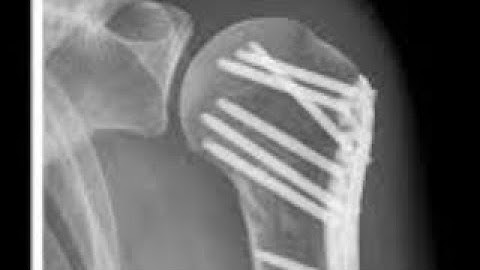

Mortality after a proximal humeral fracture